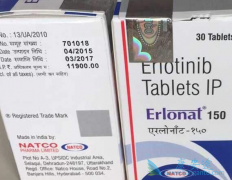

吃 印度特罗凯 耐药是否需要加量的问题,现在肿瘤大小3.8x2.7,上次没标记肿瘤大小,这种情况到底需不需要加量服用印度特罗凯呢?专家表示,首先要告诉你,印度特罗凯不主张加量使用,因为印度特罗凯的剂量确定已经是最大耐受量,如果无效,再增加剂量, ...

厄洛替尼( 印度特罗凯 )主要成份为盐酸厄洛替尼,其通用名称为盐酸厄洛替尼片,是表皮生长因子受体 (EGFR) /人表皮生长因子受体Ⅰ (也称为HER1) 的酪氨酸激酶抑制剂。临床上可以用于试用了两个或两个以上化疗方案失败的局部晚期或转移的非小细胞肺癌的 ...

肺癌晚期的靶向药,主要是依靠 印度特罗凯 和易瑞沙,也是患者最常选择的药品,主要是依托于患者对于印度特罗凯和易瑞沙的反馈来看,效果都是比较好的,但是又各自有优势,患者在不知道如何选择的时候,可以看看下文,给您一点帮助。 首先就是说一下 ...

特罗凯(厄洛替尼)是罗氏公司研发用于治疗肺癌的靶向药物,厄洛替尼单药适用于治疗既往接受过至少一个化疗方案失败后的局部晚期或转移的非小细胞肺癌患者以及用于经4个周期以铂类为基础的一线化疗后处于疾病稳定的局部晚期或转移的非小细胞肺癌患者的维 ...